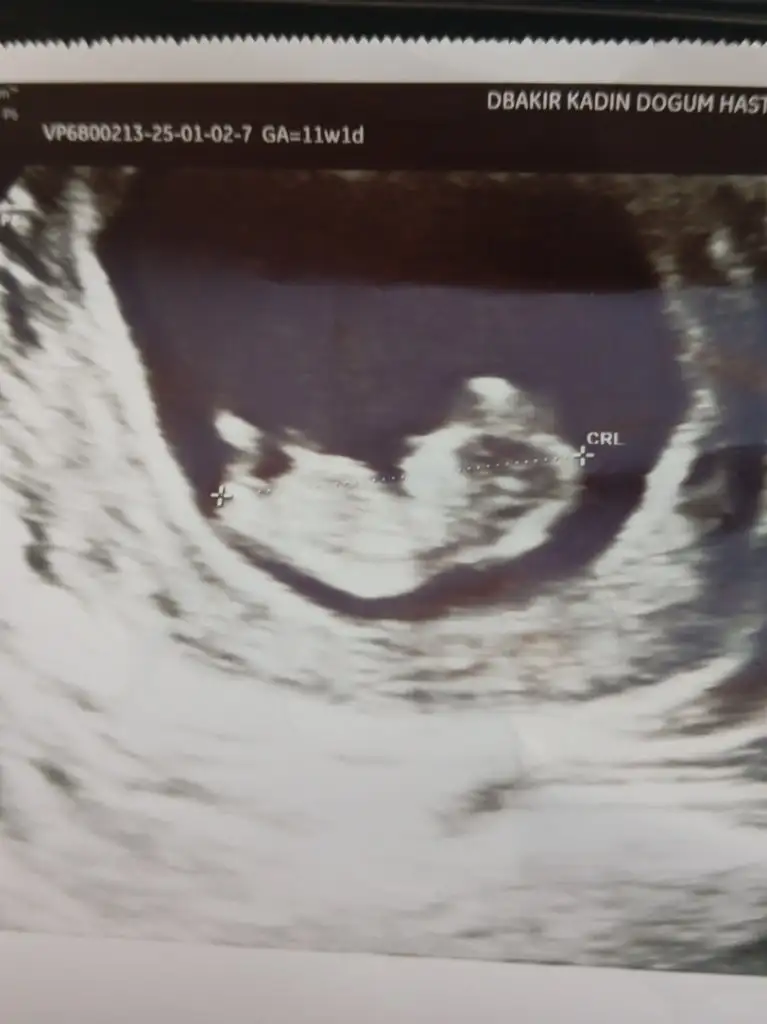

Erkek gibiiiiiiAnneler güzel anne adayları sizden rica edersem bebeğimin USG resmine cinsiyet konusunda tahmin yapabilir misiniz 11 haftalık